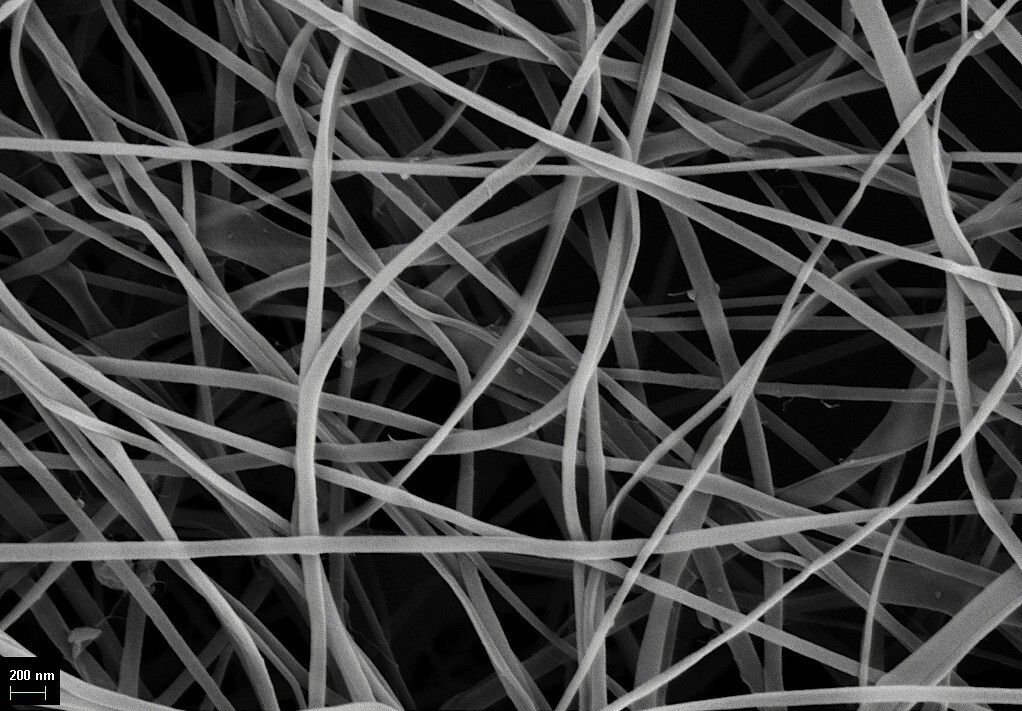

Ученые из Курского Медицинского университета разработали бинты, которые помогут контролировать процесс заживления ран с помощью специальных красителей. Эти материалы могут быть использованы при самых различных повреждениях, включая ожоги, язвы и раны у онкологических пациентов. ferra.ru »